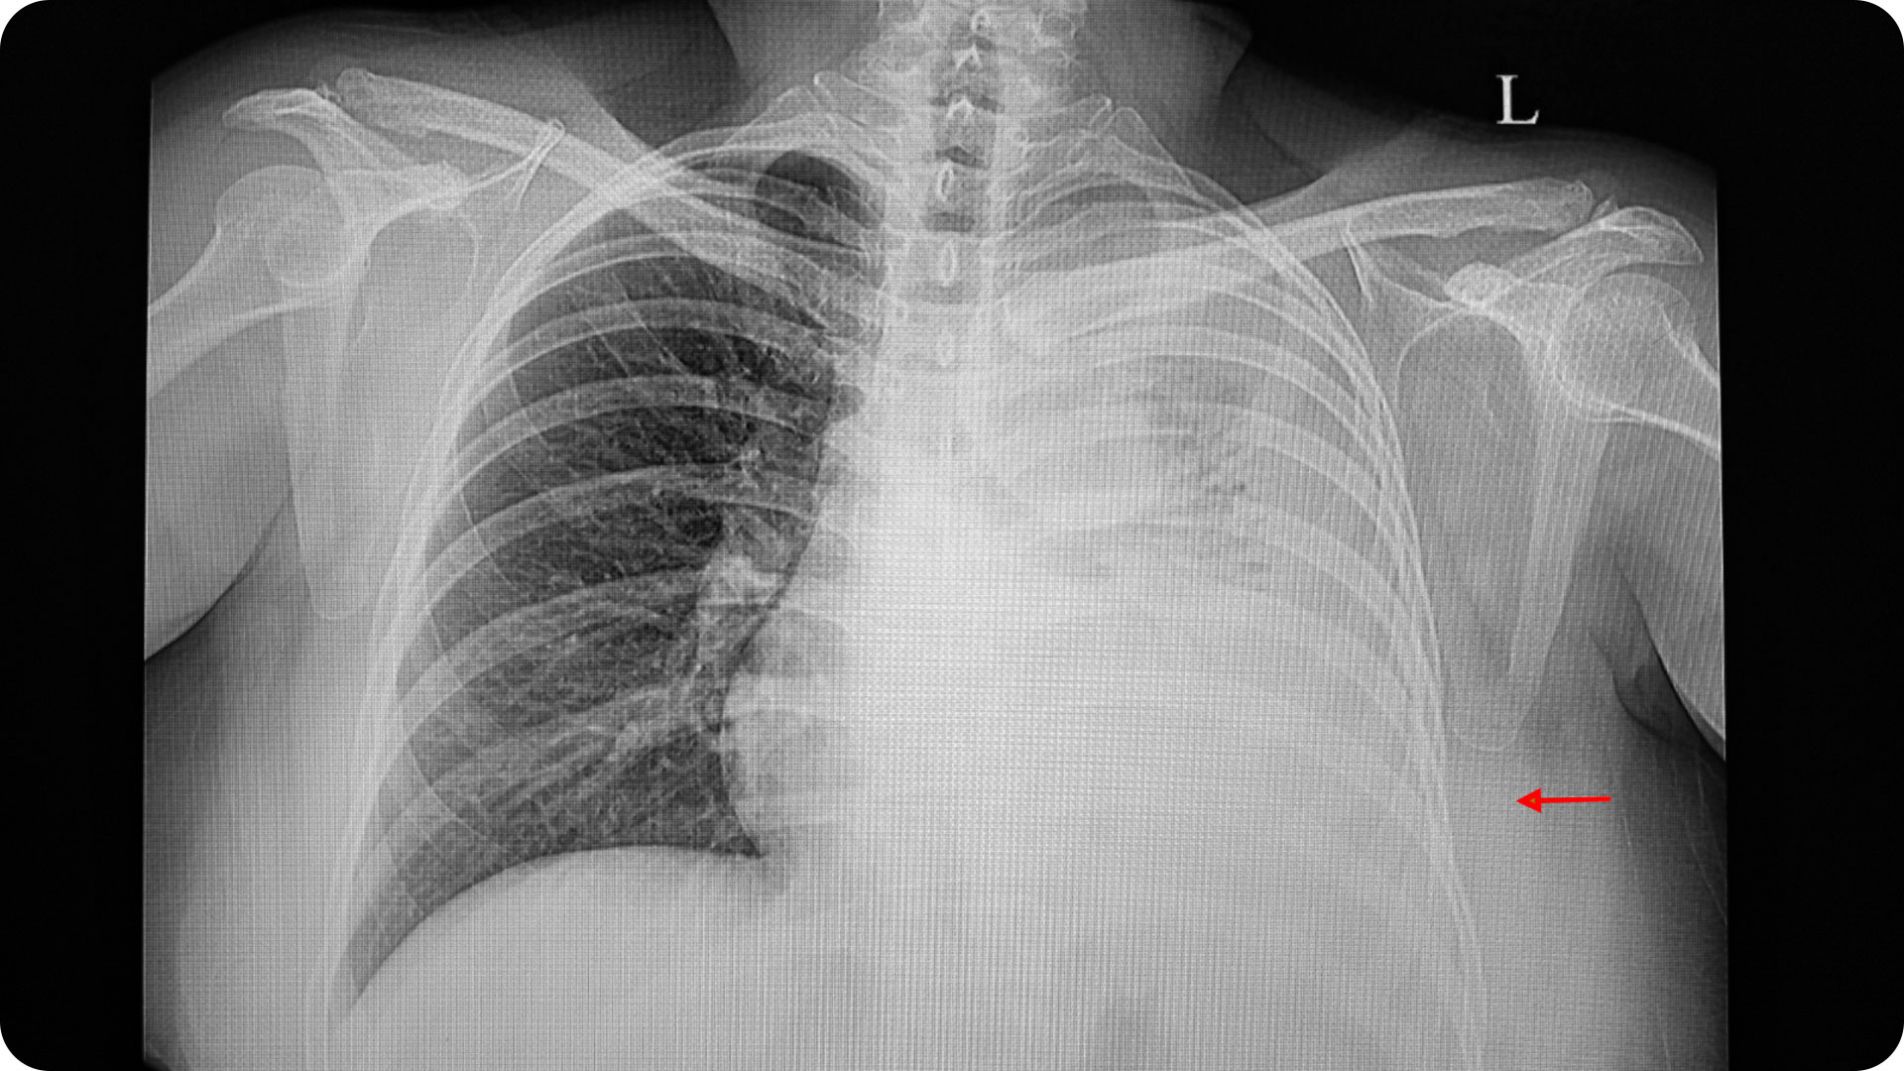

Hình ảnh X-quang ngực hiển thị tình trạng tràn dịch màng phổi một bên

X-quang ngực: Hình ảnh kinh điển là hiện tượng mờ đồng nhất ở đáy phổi và tù góc sườn hoành.